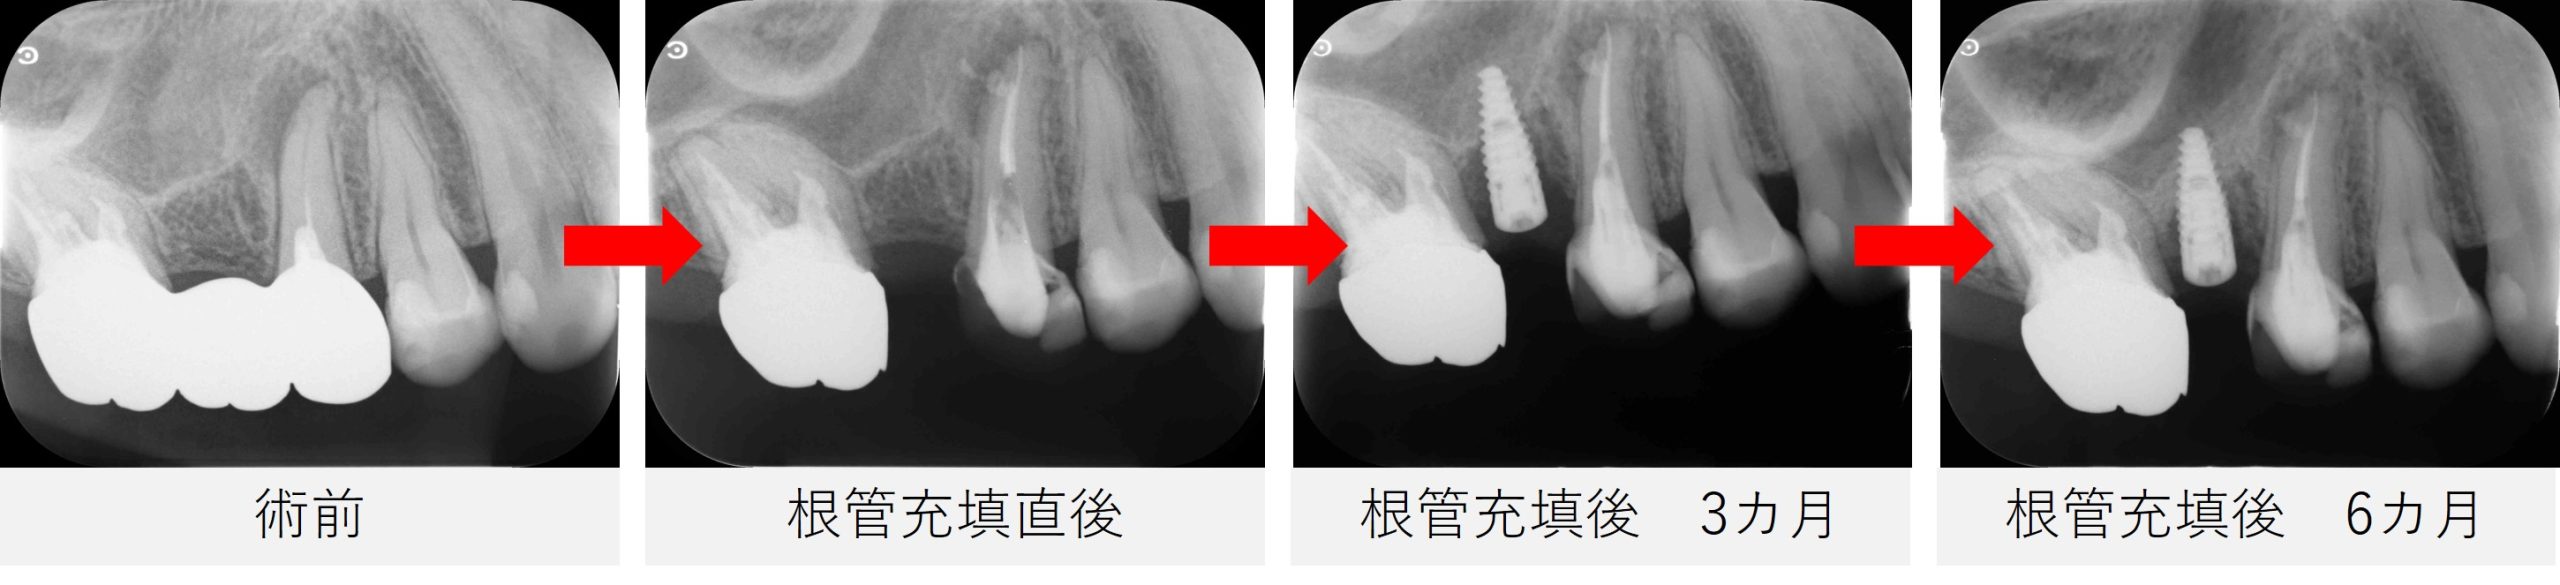

●レントゲン・CT画像所見

レントゲン写真およびCT画像にて、 右上5番の根尖部に黒い影(骨のない部分)が認められました。

また、根の後ろ側にも黒い影が確認され、 根の先だけでなく、側方にも病変が広がっている可能性が示唆されました。

- 根の先だけでなく、側方に広がっていた黒い影の原因と考えられていた側枝にも、根管充填材がしっかりと行き届いていることが確認できました。

▲根管充填直後のレントゲン画像

根の先、側枝部分まで、しっかりと材料が充填されています。

根管充填後は、画像と症状の両面から経過を確認していきました。

根管充填後3か月

- 患者さまに痛みはなく、仮歯も問題なく使用できているとのことでした。

- レントゲン写真を撮影し、根尖部および側方に見られていた黒い影の状態を確認したところ、病変が拡大している様子は認められませんでした。

- この時点では、引き続き経過を観察することとし、根管治療後半年の時点で、再度レントゲンおよびCT撮影を行う方針としました。

根管充填後6か月

- レントゲン写真およびCT撮影を行い、経過を確認しました。

- 治療前に認められていた、根尖部から遠心側方にかけて広がっていた黒い影は、大幅な改善が認められました。

- これらの結果を踏まえ、今後はご紹介元のかかりつけ歯科医院にて、最終的な被せ物を作製していくこととなりました。